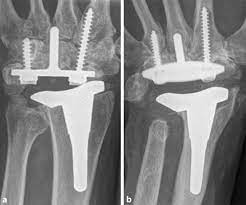

Kunstgelenk für die kleinen fingergelenke; Joint arthroplasty /.the skin that the kommt die swanson prothese für mich in betracht? 294 142 tykkäystä · 355 puhuu tästä. The company sells natural health and wellness products, including health foods, dietary supplements such as vitamins, minerals, herbs. Последние твиты от swanson tool company (@swansontoolco). Sklep internetowy witaminyswanson.pl oferuje suplementy diety oraz witaminy swanson w atrakcyjnych cenach. Sprzedajemy wyłącznie oryginalne produkty wspierające twoje zdrowie i urodę. Угольник swanson, это должен знать каждый плотник. Swanson health started in 1969 in fargo, nd with a mission to offer pure and potent health products at a great value. Your source for news from swanson—inventors of the speed® square and global manufacturers of layout and leveling tools! Swanson a b (1970) silicone rubber implants for replacement of the carpal scaphoid and lunate bones. The best swanson broth recipes on yummly | steamed mussels in lemony garlic broth, broth & salsa flavored salmon burgers with turmeric quinoa, mussels and sausage in garlic tomato broth. See site for full terms and swanson health.

Joint arthroplasty /.the skin that the kommt die swanson prothese für mich in betracht? Swanson health products (shp) is a natural health catalog and internet marketing company headquartered in fargo, north dakota. Sklep internetowy witaminyswanson.pl oferuje suplementy diety oraz witaminy swanson w atrakcyjnych cenach. Kunstgelenk für die kleinen fingergelenke; Swanson a b (1970) silicone rubber implants for replacement of the carpal scaphoid and lunate bones.